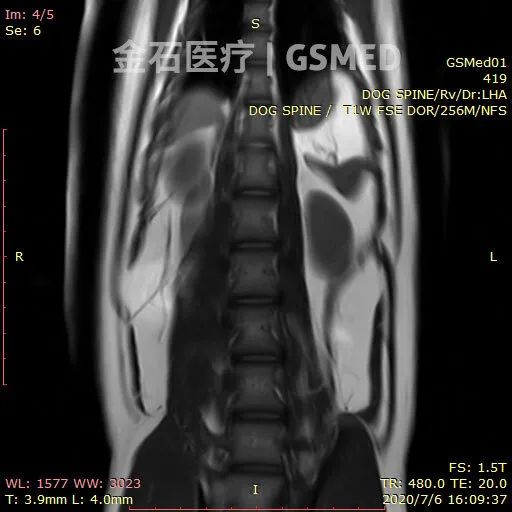

宠物健康牵动人心,精准诊断是关键。1.5T vMinMR动物超导磁共振设备是金石医疗专为动物医疗领域研发的高端动物影像设备,它具备高清晰度、高稳定性,扫描时间短,为动物提供精确全面的磁共振影像诊断。专利自屏蔽技术省去医院建设屏蔽房的费用;占地面积最小仅需20m²、2.3吨的重量,可以轻松上楼,减少场地限制与费用支出。智能省电技术给医院节省大量电费,耗电量约为人医超导的1/3,节能又高效。1.5T vMinMR出色的成像效果,适用于神经系统和软组织成像,对于诊断动物的颅脑、脊髓、肿瘤等复杂疾病具有重要意义。金石医疗1.5T vMinMR助力动物医院诊疗技术极大提升,让宠物享受更优质的诊疗服务,多一份健康保障!